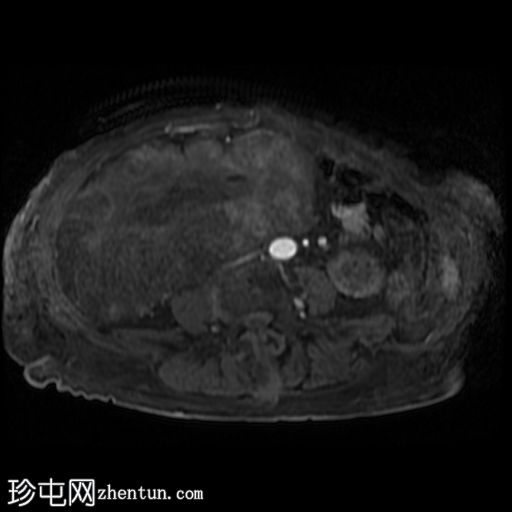

5.jpeg

轴位 T2

脂肪抑制

右髂窝移植肾不规则且受压,肾周可见巨大分叶状肿块,T2呈高信号,并进行性不均匀强化。这是黏液样变性的典型表现。